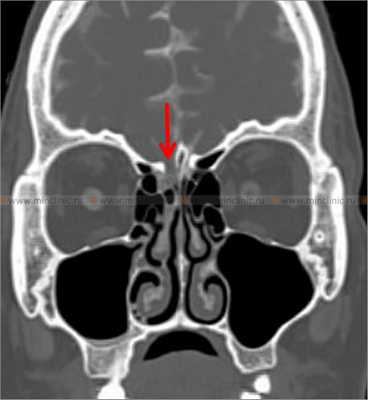

При компьютерной томографии костей черепа с цистернографией визуализируется костный дефект правой решетчатой пластинки (указано красной стрелкой).